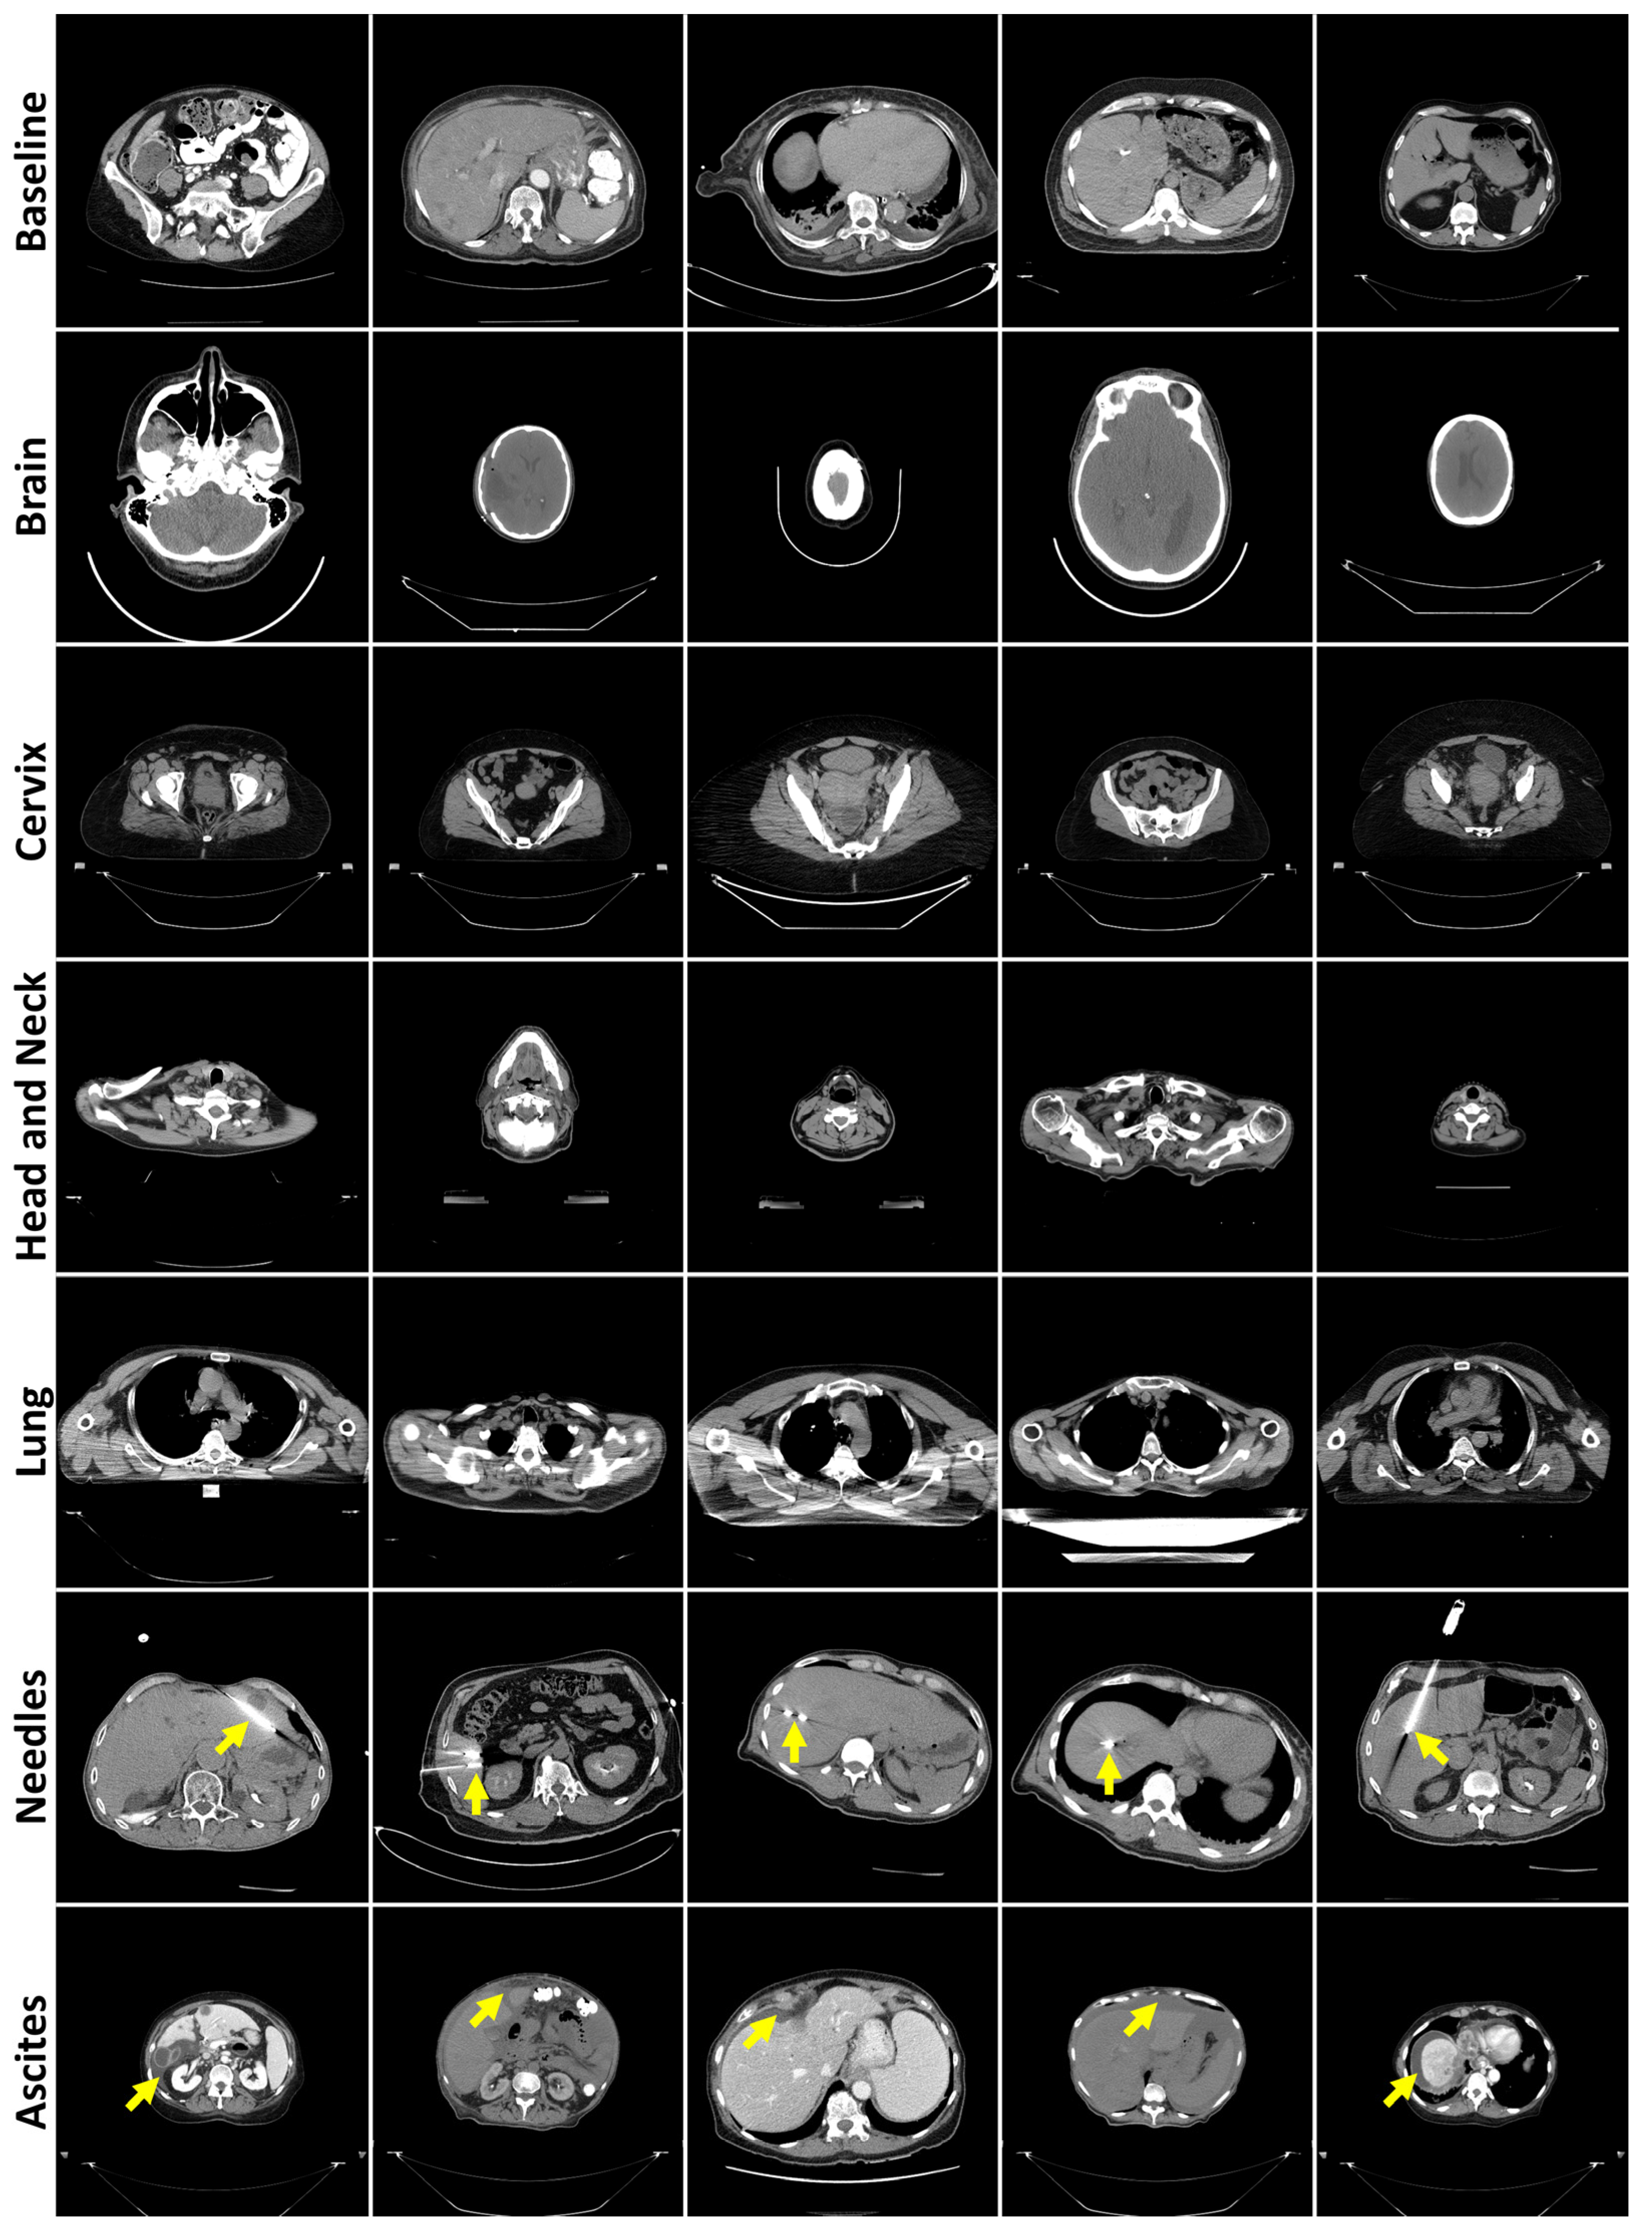

3.1. Evaluation of Generated Image Quality

3.2. Reconstruction Performance and Interpretation